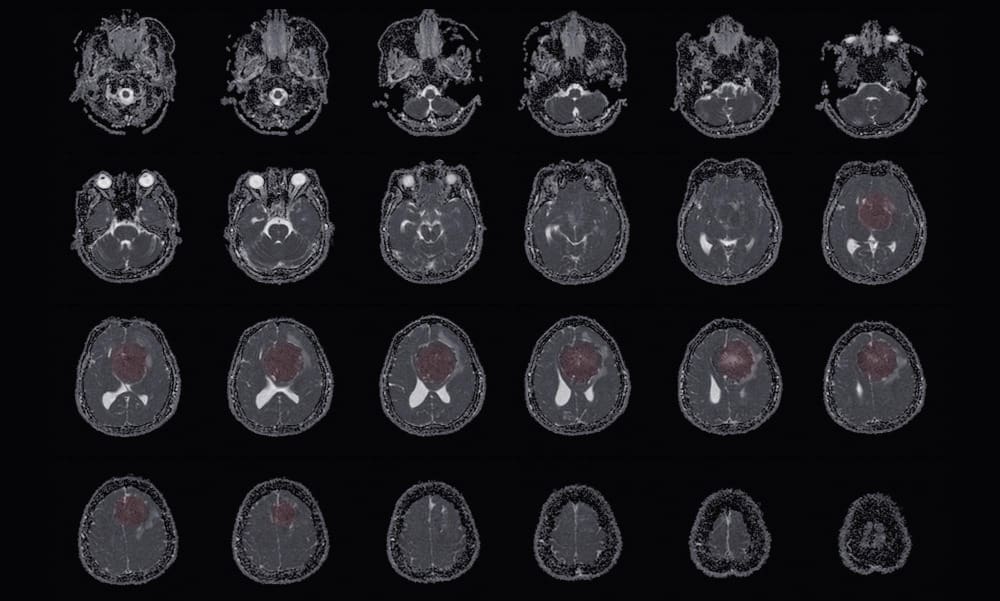

meningioma

Can You Die From a Benign Meningioma? Life Expectancy, Grades, and Survival Explained 3

Benign meningiomas are tumors that grow from the meninges. These are protective membranes around the brain and spinal cord. Knowing about these tumors is key for patients to understand their health situation.